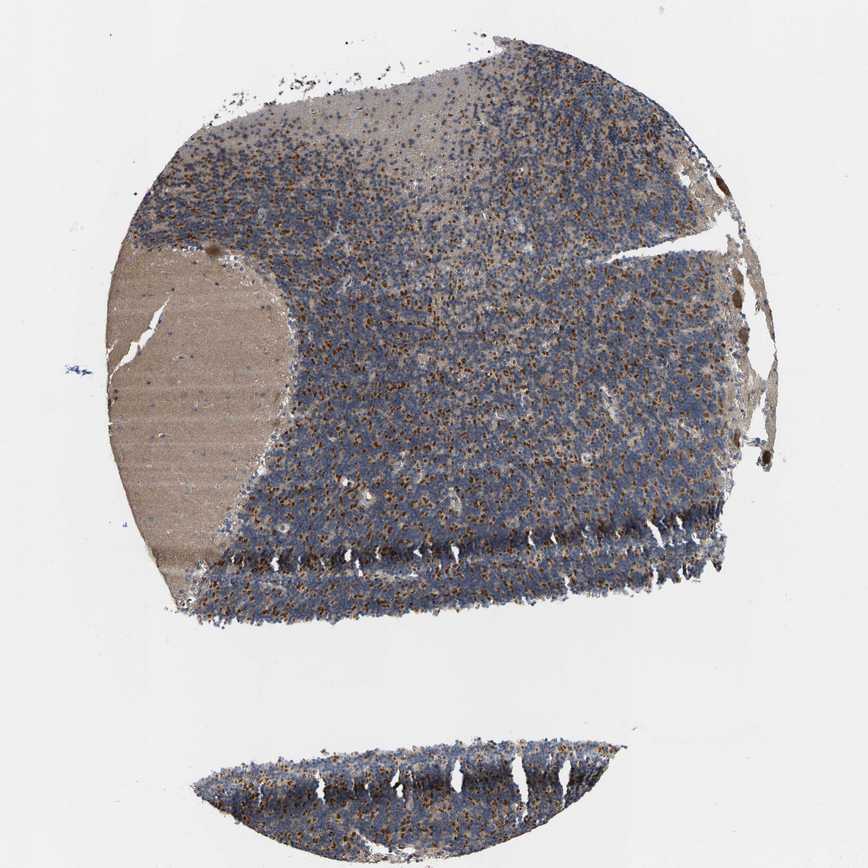

CEREBELLUM - Antibody stainingi

Antibody staining in the annotated cell types in the current human tissue is reported as not detected, low, medium, or high, based on conventional immunohistochemistry profiling in selected tissues. This score is based on the combination of the staining intensity and fraction of stained cells.

Each image is clickable and will lead to virtual microscopy that enables deeper exploration of all samples and also displays staining intensity scores, fraction scores and subcellular localization as well as patient and tissue information for each sample.

Antibody HPA016419Antibody HPA019625

Purkinje cells LowMedium

Cells in granular layer LowMedium

Cells in molecular layer Not detectedNot detected